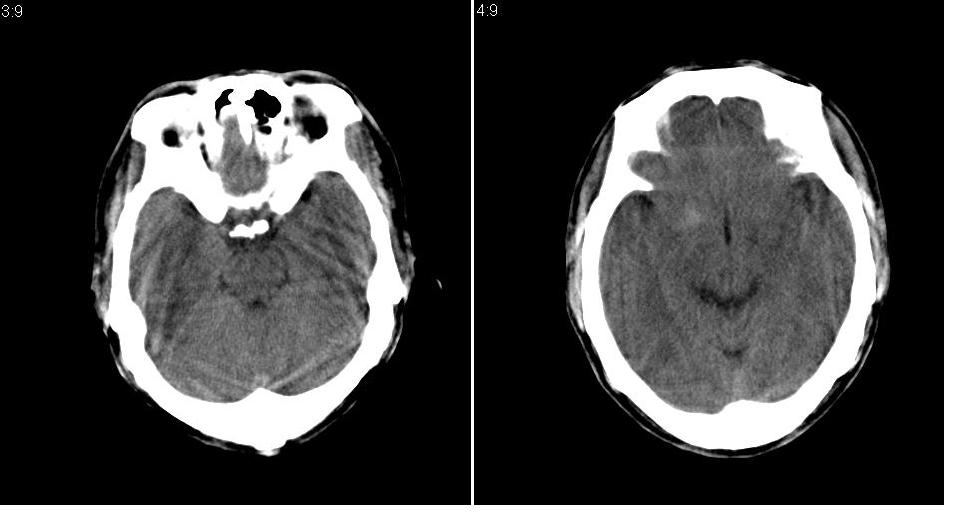

以下是引用tianhep在2007-5-9 19:53:00的发言:[br]这个部位多为苍白球钙化,苍白球钙化往往双侧对称。有外伤史而无症状。首先考虑为苍白球钙化。短期内复查一次就可。

以下是引用狙击手在2007-5-9 19:52:00的发言:[br]病灶边界模糊,外周无水肿带,无占位效应,无任何不适,考虑钙化。

以下是引用gyh6308在2007-5-9 21:10:00的发言:[br]这种病例我见过,是脑血管畸形所致的钙化,做cta可观察